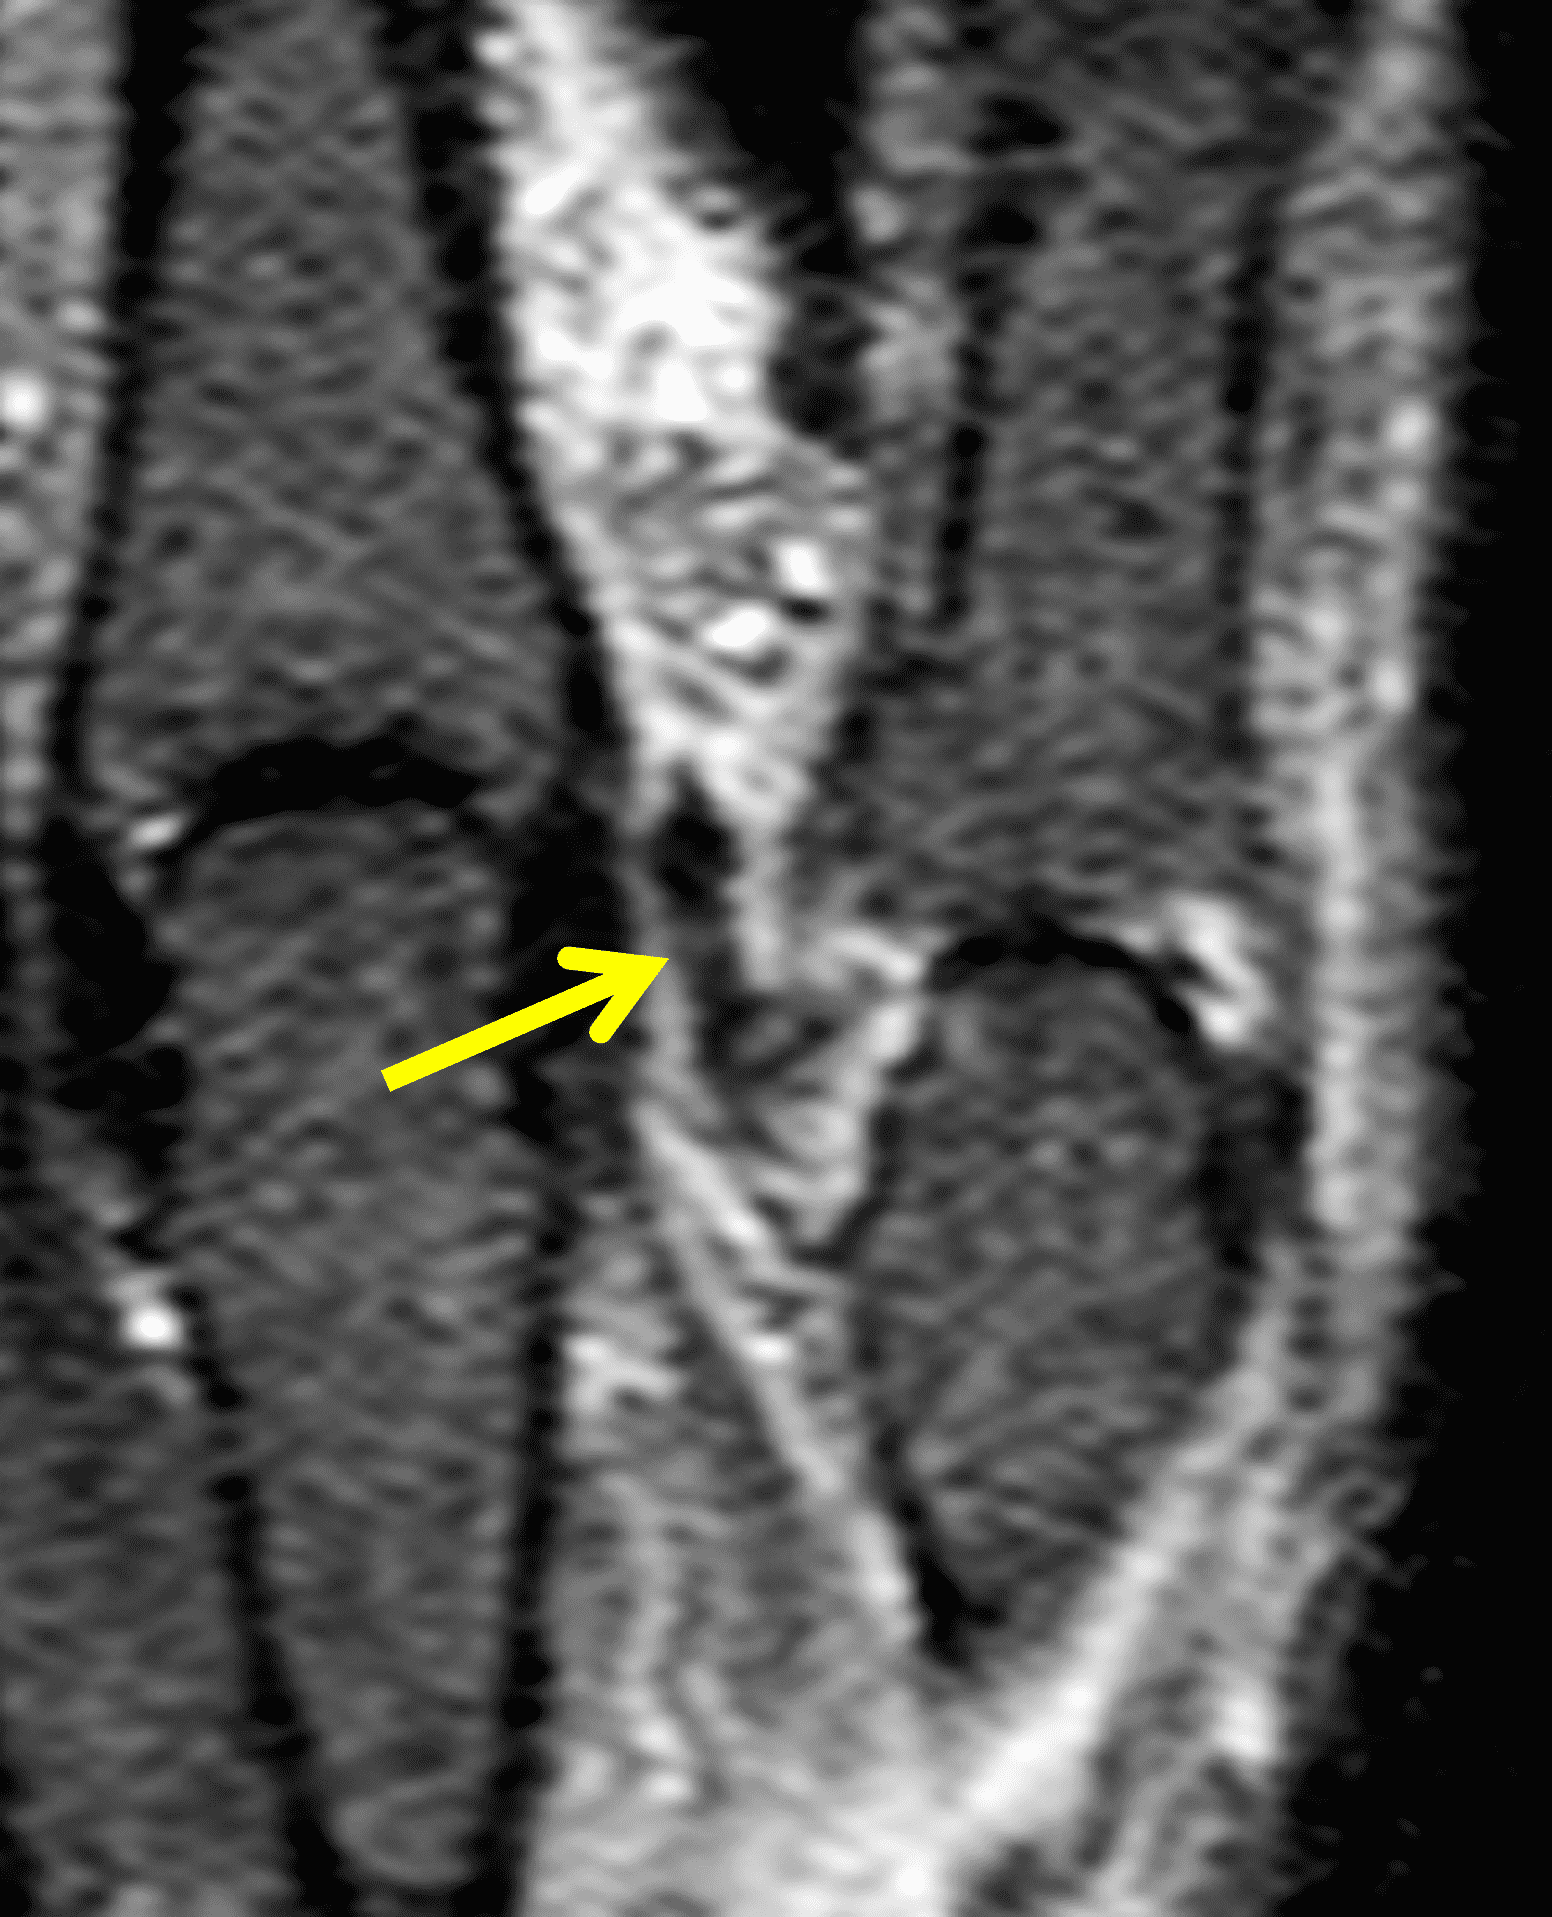

A 30-year-old male presents with pain at the metacarpophalangeal (MP) joint of the thumb following a bicycle wreck. Coronal proton density-weighted (Figure 1A) and inversion recovery (Figure 1B) images, and consecutive axial proton density-weighted images (Figure 1C and 1D) are provided. What are the findings? What is your diagnosis?

Figure 2: The coronal images (2A and 2B) reveal a complete tear of the thumb MP joint ulnar collateral ligament (UCL) from its distal insertion. The torn ligament (arrows) is retracted proximal to the adductor aponeurosis (arrowhead), best seen on the proton density-weighted sequence, and the torn ligament points ulnarly rather than distally. The adductor aponeurosis (arrowheads) is fully visualized in the axial plane at the metacarpal head (2C). An axial slice (2D) just proximal the aponeurosis reveals the balled-up, retracted UCL (arrow).

Complete distal disruption of the ulnar collateral ligament at the MP joint of the thumb, with a Stener lesion.